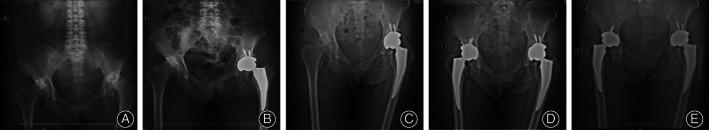

From March 2012 to May 2014, we retrospectively reviewed 84 patients (104 hips) who received Tri-Lock (BPS) and 84 patients (115 hips) who received conventional standard Corail stem in THA. Their mean ages were 53.12 ± 2.32 years and 52.00 ± 2.11 years, respectively. The clinical outcomes were assessed by Western Ontario and McMaster University Osteoarthritis Index (WOMAC), Pain Visual Analogue Scale (VAS) and Harris Hip Score (HHS). The radiological outcomes were evaluated by the radiological examination. Accordingly, Intraoperative and postoperative complications were observed as well.

The mean follow-up time was 48.23 ± 2.91 months in the Tri-Lock (BPS) group and 49.11 ± 2.11 months in the Corail group, respectively. The bleeding volumes in two groups were comparable (169.22 ± 58.11 mL vs 179.30 ± 59.14 mL, P = 0.003), with more bleeding volume in Corail group patients, while no statistically significance with respect to operation time was observed (65.41 ± 6.24 min vs 63.99 ± 6.33 min, P = 0.567). The rates of intraoperative fracture was 8% for the Corail group while 1% for the Tri-Lock (BPS) group (8% vs 1%, P = 0.030). At final follow-up, no statistical differences in regard to HHS, WOMAC, and Pain VAS were revealed between the two groups (P > 0.05). The rate of thigh pain was higher in Corail group than in Tri-lock (BPS) group (5% vs 0%, P = 0.043). However, incidence of stress shielding in grade 1 was higher in Tri-Lock (BPS) than in the Corail group (76% vs 23%, P < 0.01), while those in grade 2 and 3 were lower compared to the Corail stem (15% vs 28%, P < 0.01; 9% vs 16%, P = 0.008, respectively). Intriguingly, other assessments in relation to radiographic outcomes and postoperative complications were not comparable between the two groups. The Kaplan-Meier survival rate (revision surgery performed for any reason was defined as the end point) was similar between the two groups (P = 0.57), with 98.8% (95% confidence interval, 92.3%-100%) in Tri-lock (BPS) group and 97.6% (95% confidence interval, 94.6%-100%) in Corail group.

The Tri-Lock (BPS) has similar clinic performances compared to the Corail stem. Furthermore, the Tri-lock (BPS) stem has some advantages in achieving lower incidence of thigh pain, stress shielding and intra-operative fracture. Therefore, we recommend the Tri-lock (BPS) stem as a good alternative in primary total hip arthroplasty, especially taking into account patient factors, including bone deficiency and convenience of extraction of the stem in hip revision.